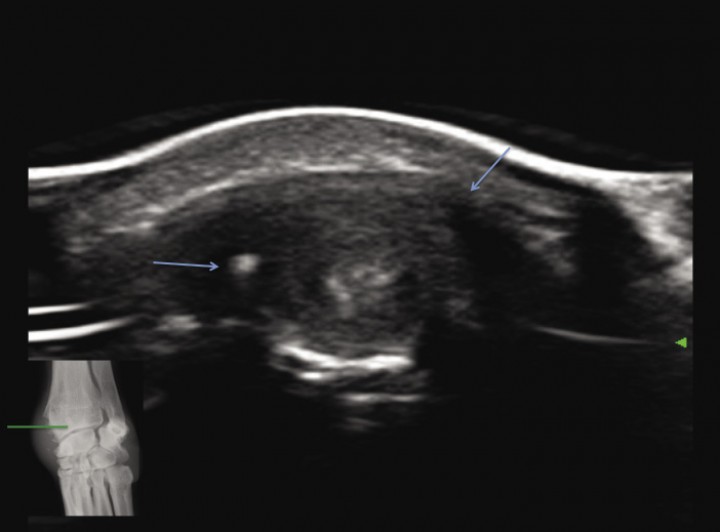

Para corroborar nuestras sospechas de afección del tendón abductor pollicis longus se realiza una ecografía con transductor lineal de alta frecuencia (Esaote MyLab Class C, 4- 13 MHz). Sobre un corte longitudinal de la cara dorsomedial del radio distal (Fig. 3) apreciamos marcado engrosamiento del tendón abductor pollicis longus sin pérdida del patrón de fibras (flecha amarilla) así como del tejido periférico que lo engloba (flechas azules), con presencia de efusión dentro de la vaina tendinosa (asterisco rojo). La superficie ósea se aprecia irregular, indicando reactividad del hueso cortical subyacente (flecha naranja). No se observan indicios de inflamación intrarticular o presencia de osteofitosis en la articulación radiocarpiana, intercarpiana o carpometacarpiana (Fig. 3). Estos hallazgos se observan de manera clara mediante cortes transversales a lo largo del tendón (Fig. 4), donde se puede identificar la neoformación ósea “englobando” el tendón abductor especialmente en la inserción de la vaina tendinosa al radio distal.

<p>Imagen en corte transversal del radio distal donde se aprecia neoformación ósea periférica (flechas azules) al surco por donde discurre el tendón tendón abductor <em>pollicis longus</em> y su vaina, marcadamente engrosada.</p>

Imagen en corte transversal del radio distal donde se aprecia neoformación ósea periférica (flechas azules) al surco por donde discurre el tendón tendón abductor pollicis longus y su vaina, marcadamente engrosada.